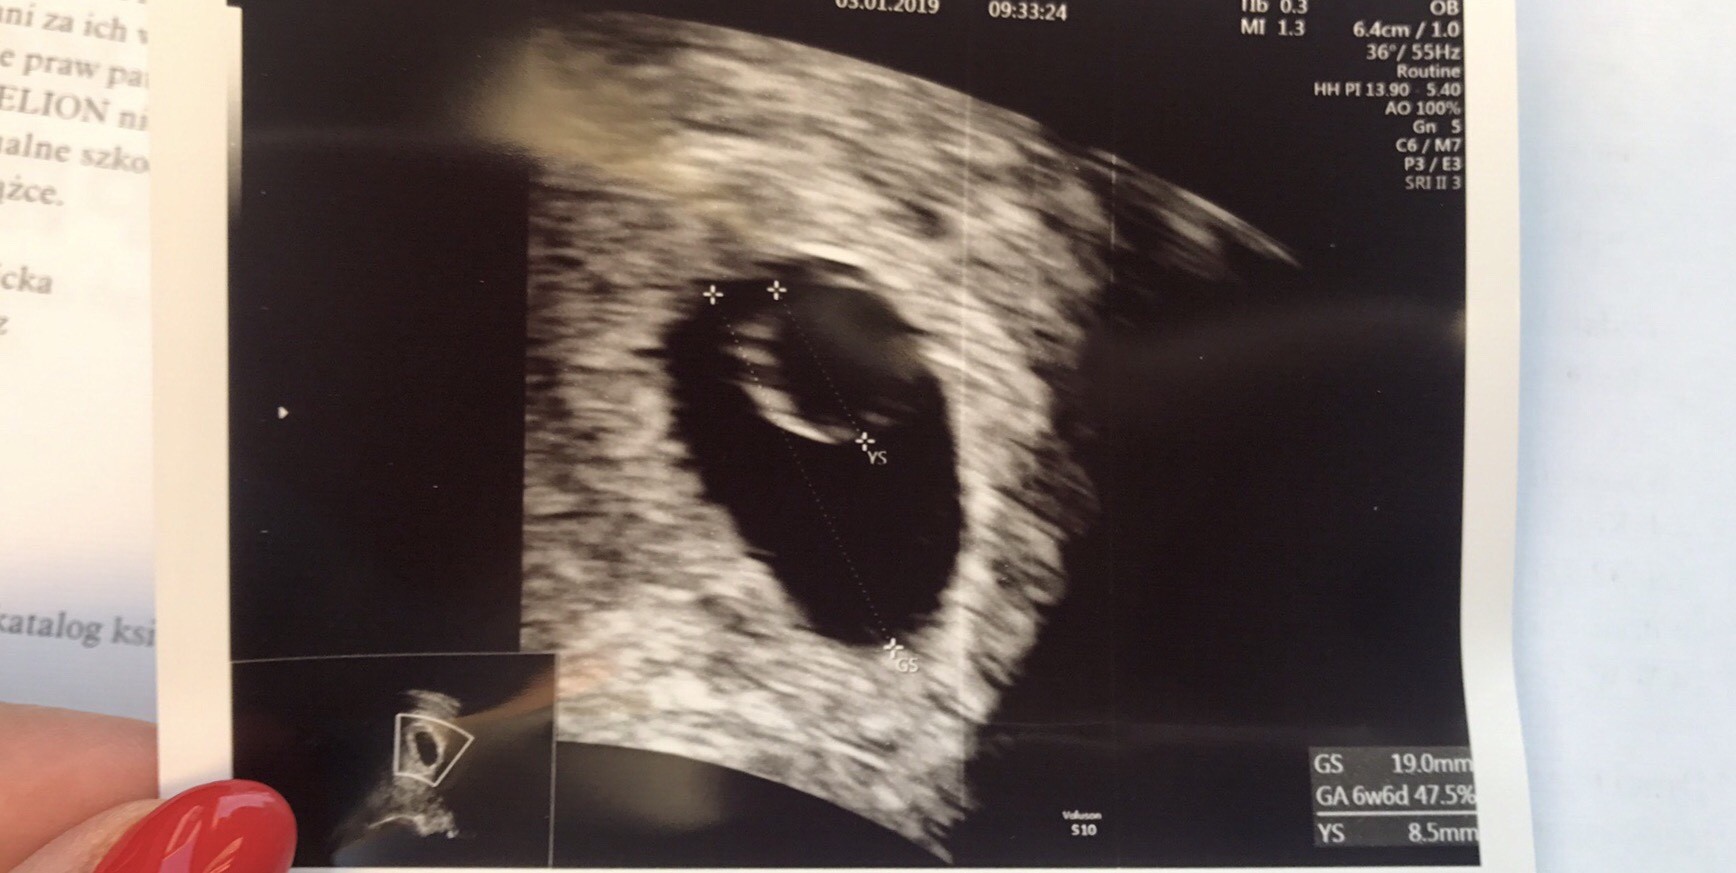

Dziewczyny, nie ukrywam ze liczylam na serduszko dzisiaj ale wyglada na to ze musze poczekac jeszcze kilka dni. Lekarce wyszlo 6t6d, ona mowi ze wszystko w jak najlepszym porzadku a lada dzien powinnismy juz cos widziec. Ja mialam transfer 1 grudnia ale to byla bardzo slaba blastka.

Ja oczywiscie sie obawiam troche ale moze rzeczywiscie jest za wczesnie. A wiec czekamy do poniedzialku.

Na pewno wszystko bedzie w jak najlepszym porzadku. Teraz serduszko to kwestia dnia czy dwoch skoro jest yolk sack.